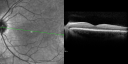

OD: Vertical C/D ratio is 0.2. There is no posterior vitreous separation and 2+ multiple macular drusen. There is no bull’s-eye maculopathy.

OS: Vertical C/D ratio is 0.2. There is no posterior vitreous separation, again there are 2+ multifocal small cuticular macular drusen.

OCT SCAN: The OCT scans were normal. Photos confirm clinical findings.

FLUORESCEIN ANGIOGRAPHY: Fluorescein angiography shows early hyperfluorescence of tiny macular drusen scattered throughout the macula in both eyes.